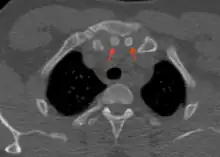

Axial computed tomography showing the episternal ossicles (red arrows)

The episternal ossicles are oval-shaped bones that are occasionally found at the superior and posterior border of the manubrium. The episternal ossicles were first described by Cobb in 1937.[2] They may be present unilaterally or bilaterally.[3] Its size ranges from 2–15 mm depending on individuals.[4] These ossicles are asymptomatic and does not cause any harm, although it may be diagnosed as fracture, vascular ossification or calcified lymph nodes.